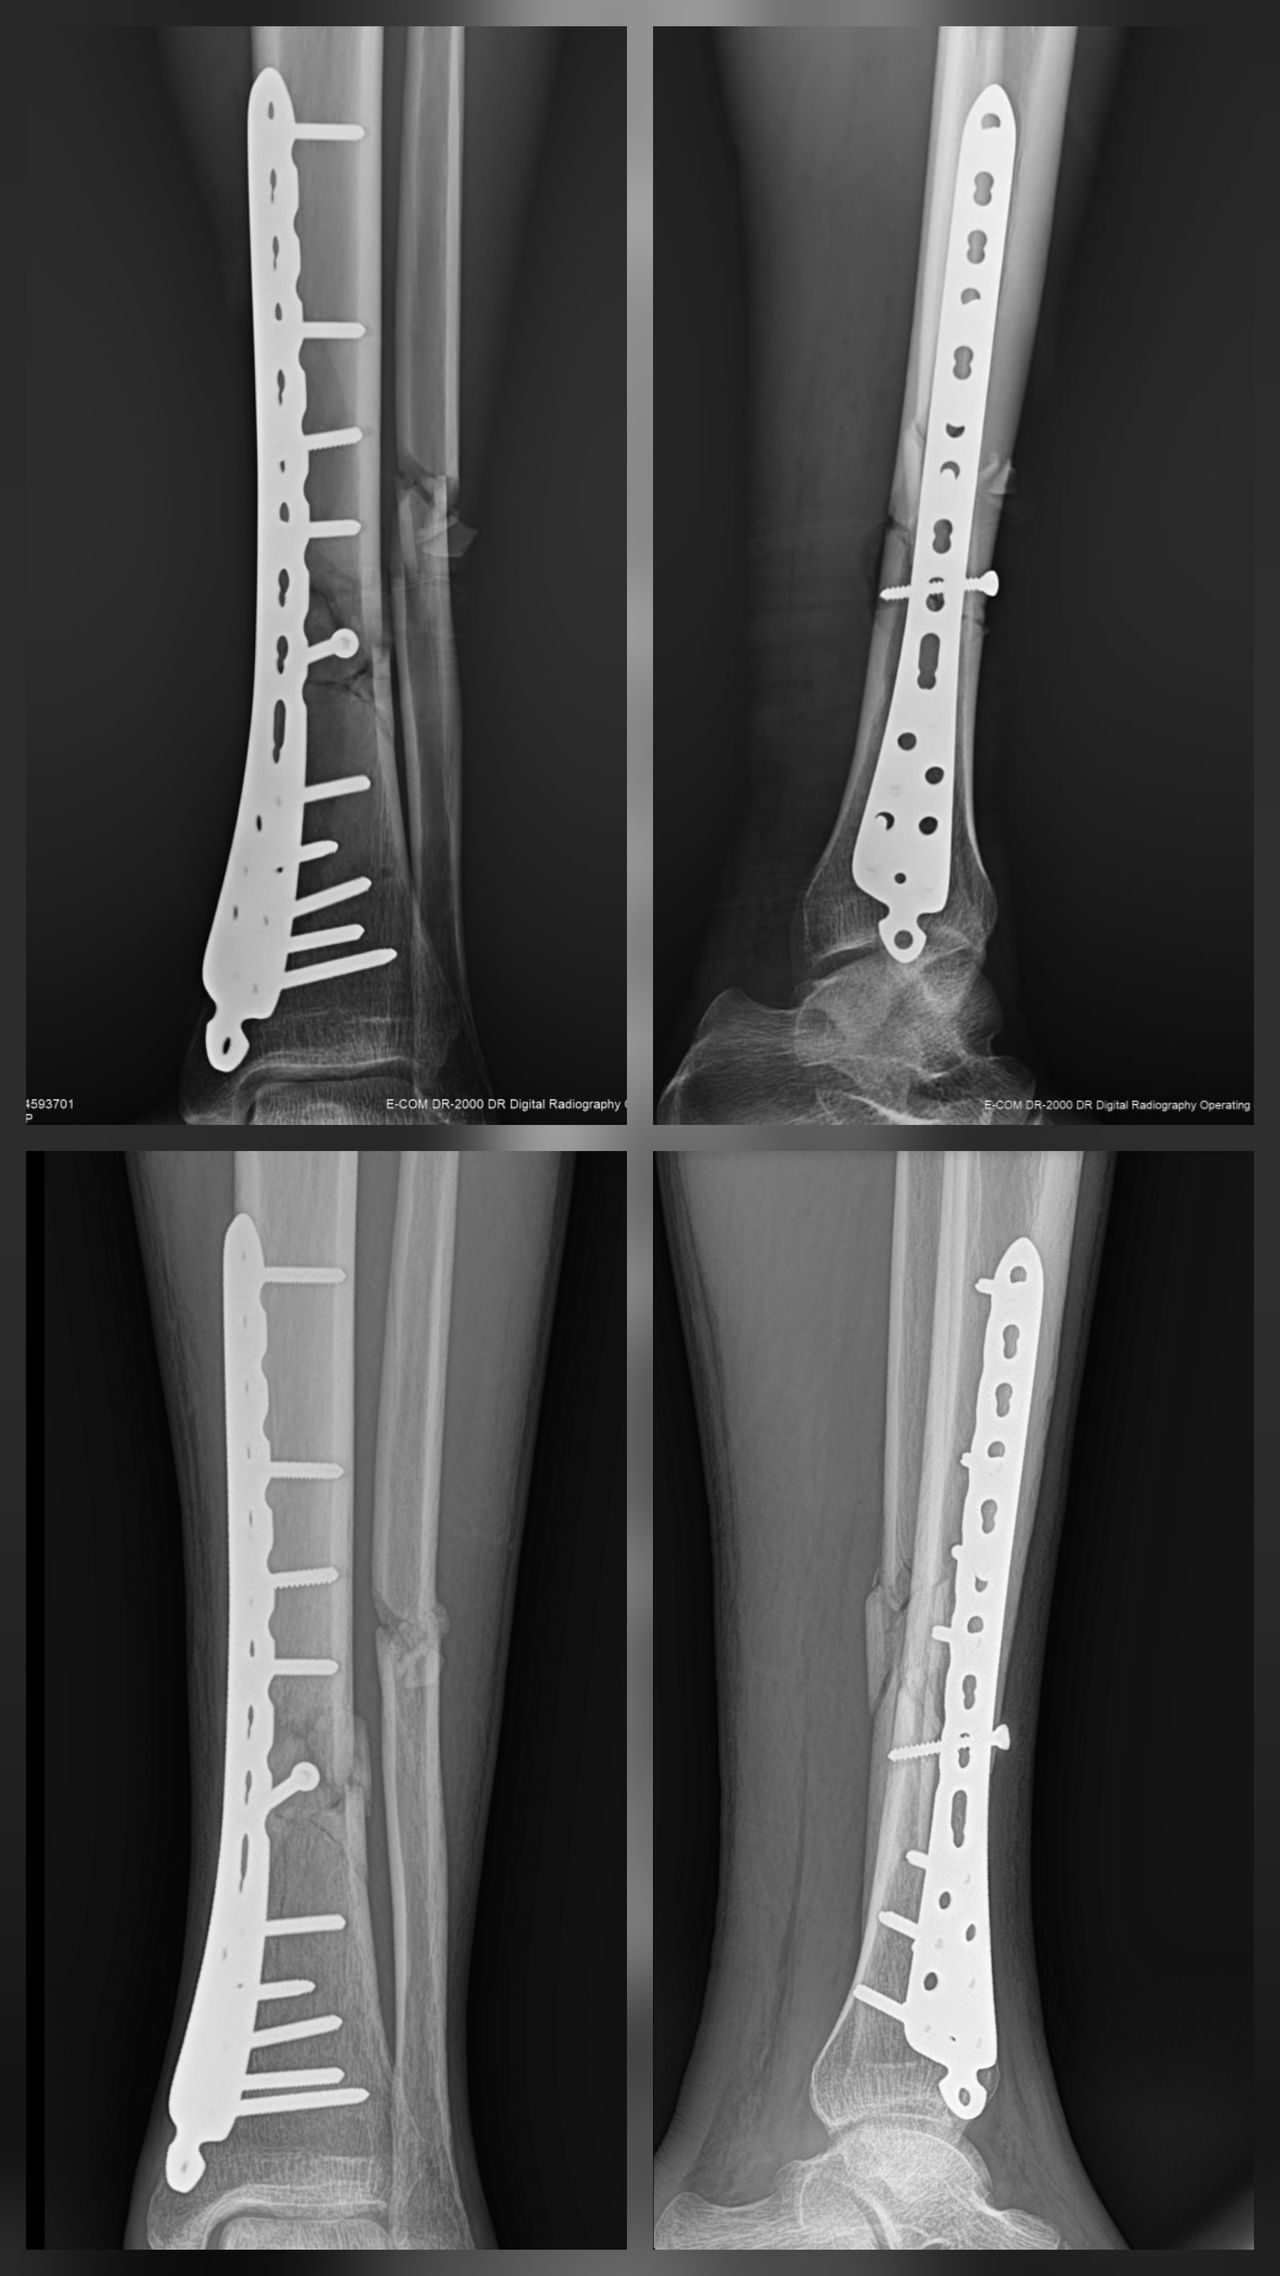

Mis habilidades más fuertes son el manejo de padecimientos de rodilla, cadera y hombro, así como procedimientos quirúrgicos asociadas a enfermedades degenerativas, fracturas y luxaciones.